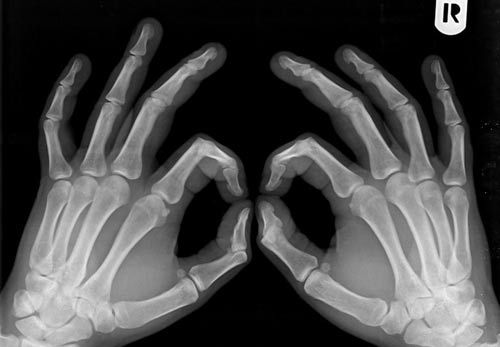

هناك مؤشرات تدل على الإصابة بهذا المرض وهي تُعدّ كعلامات لهشاشة العظام، من بينها فقدان طول الجسم وآلام الظهر، ويمكن التأكد من وجود خلل أو هشاشة في العظام عن طريق الأشعة "السينية" أو عبر جهاز قياس كثافة العظم الذي يدل على الخلل الحاصل بالنسبة لعمر المريض.